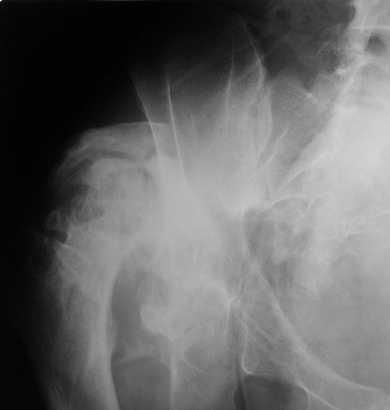

Уважаемые коллеги. Пациент 30 лет 3 года назад в результате травмы получил травматический дефект нижних конечностей до в/3 голеней, был пропущен вывих бедра.

В настоящее время очень неплохо ходит на протезах, движения в неоартрозе близки по объему к здоровой стороне. Основная жалоба - выраженная боль при ходьбе. планируем двухэтапное эндопротезирование - задним доступом мобилизовать проксимальный отдел бедра, резецировать шейку, аппаратом низвести бедро(головку оставить там где она есть, так как больших дефектов не видно(может пригодится в последующем?)). Вторым этапом бесцементное эндопротезирование. Насколько такой вариант реалистичен? Доступ для второго этапа? Может быть другие варианты?С уважением, Максим

На последнем срезе КТ задний край практически отсутсвует по сравнения со здоровой стороной. Разумеется, что это плоскостное изображение, но головка вывихнулась не только в плоскостную щель захваченную на КТ. Если вы считаете, что удастся установить туда чашку даже низкопрофильную, остается пожелать вам успехов. Но перед этим можно смоделировать установку чашки на скиаграммах КТ.

За пожелание успехов - спасибо, думаю это пригодится, не очень понял про плоскостную щель, специально предоставил срезы на уровне свода - он цел, дефект заднего края ниже, за счет заглубления он будет еще меньше, по данным 3d - должно получиться.